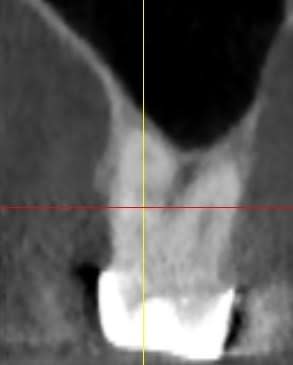

Je vous met la pano complète ainsi que des détails qui je l'espère seront suffisants pour vous faire une idée.

Les hauteurs que j'ai pu indiquer comporte aussi de la dentine infiltrée, pardonnez moi de le préciser.

La 26 on dirait que l'os vestibulaire est mini. quant au reste je ne vois pas comment mettre des tenons pour conserver suffisamment de trt radiculaire.